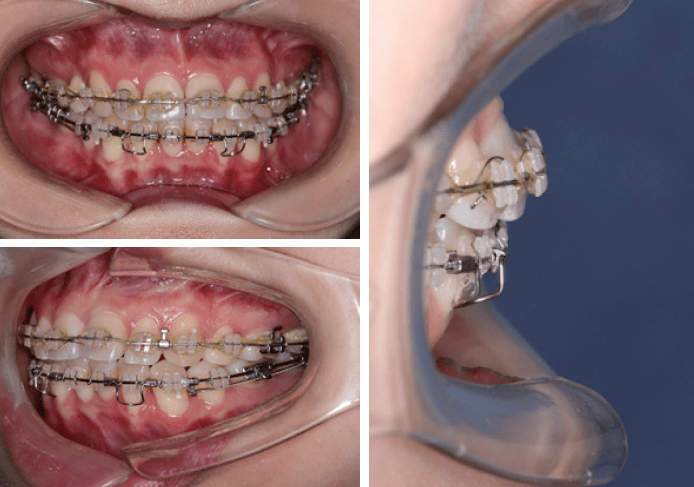

《正畸案例41:正畸中的骨开裂与骨开窗》

《正畸案例41:正畸中的骨开裂与骨开窗》

如果一旦发生了前牙骨开裂或骨开窗,应该怎么办?